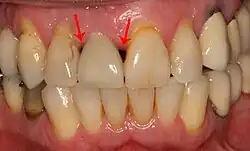

Fehlender Approximalkontakt zwischen dem rechten seitlichen Schneidezahn (Zahn 12) und dem Eckzahn (Zahn 13).